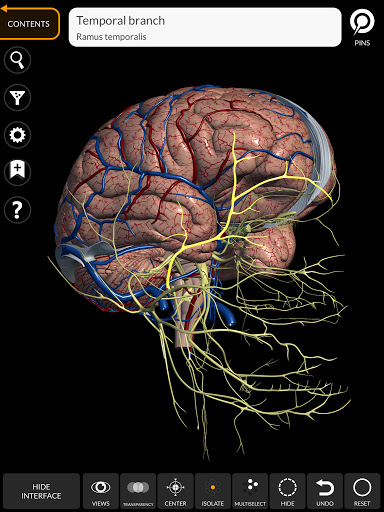

يتيح لك "Anatomy 3D Atlas" دراسة التشريح البشري بطريقة سهلة وتفاعلية.

من خلال واجهة بسيطة وبديهية، من الممكن ملاحظة كل بنية تشريحية من أي زاوية.

تتميز النماذج التشريحية ثلاثية الأبعاد بتفاصيل خاصة ودقة تصل إلى 4K.

• الجهاز العصبي

• من خلال تحديد نموذج أو دبوس، يظهر المصطلح التشريحي ذي الصلة